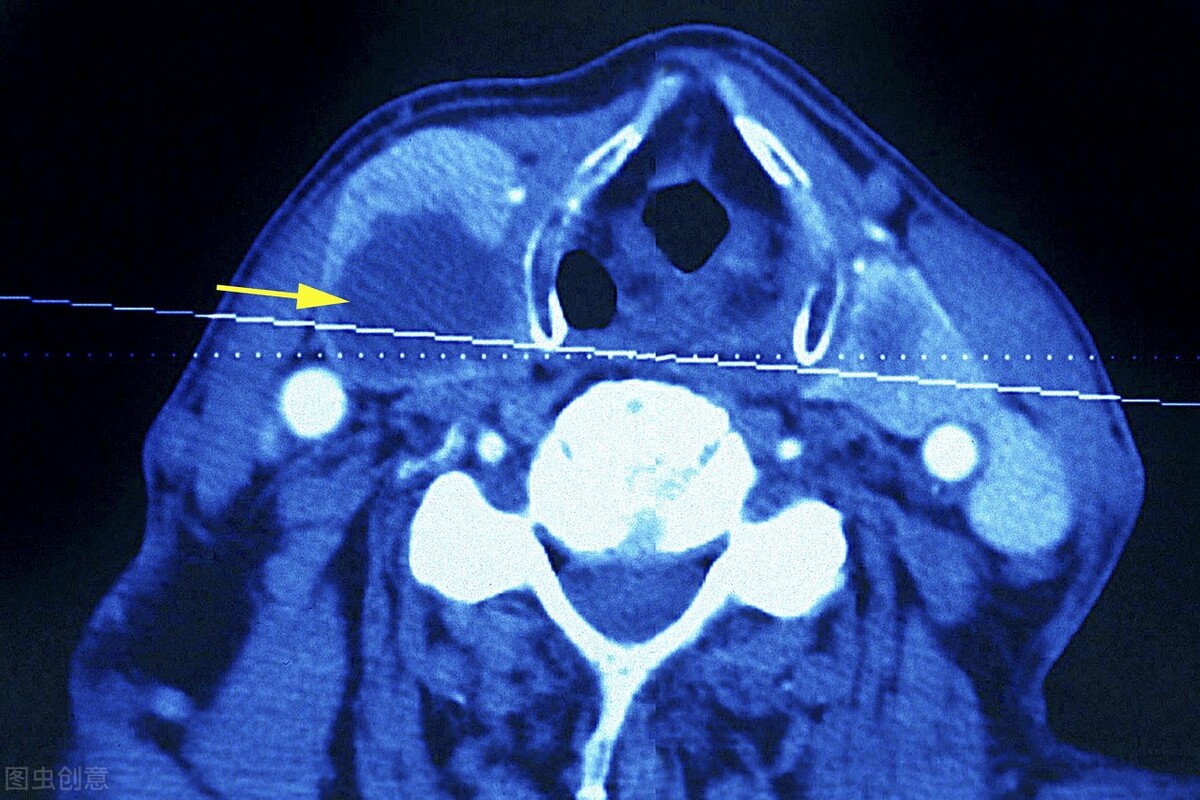

这种技术是在高分辨率B超的引导下,精确制导,精准定位,让病变组织产生生物高热效应,使结节、囊肿等组织在热凝过程中脱水、凝固、凋亡、坏死,最后被机体自然吸收,从而达到治愈甲状腺结节的目的。